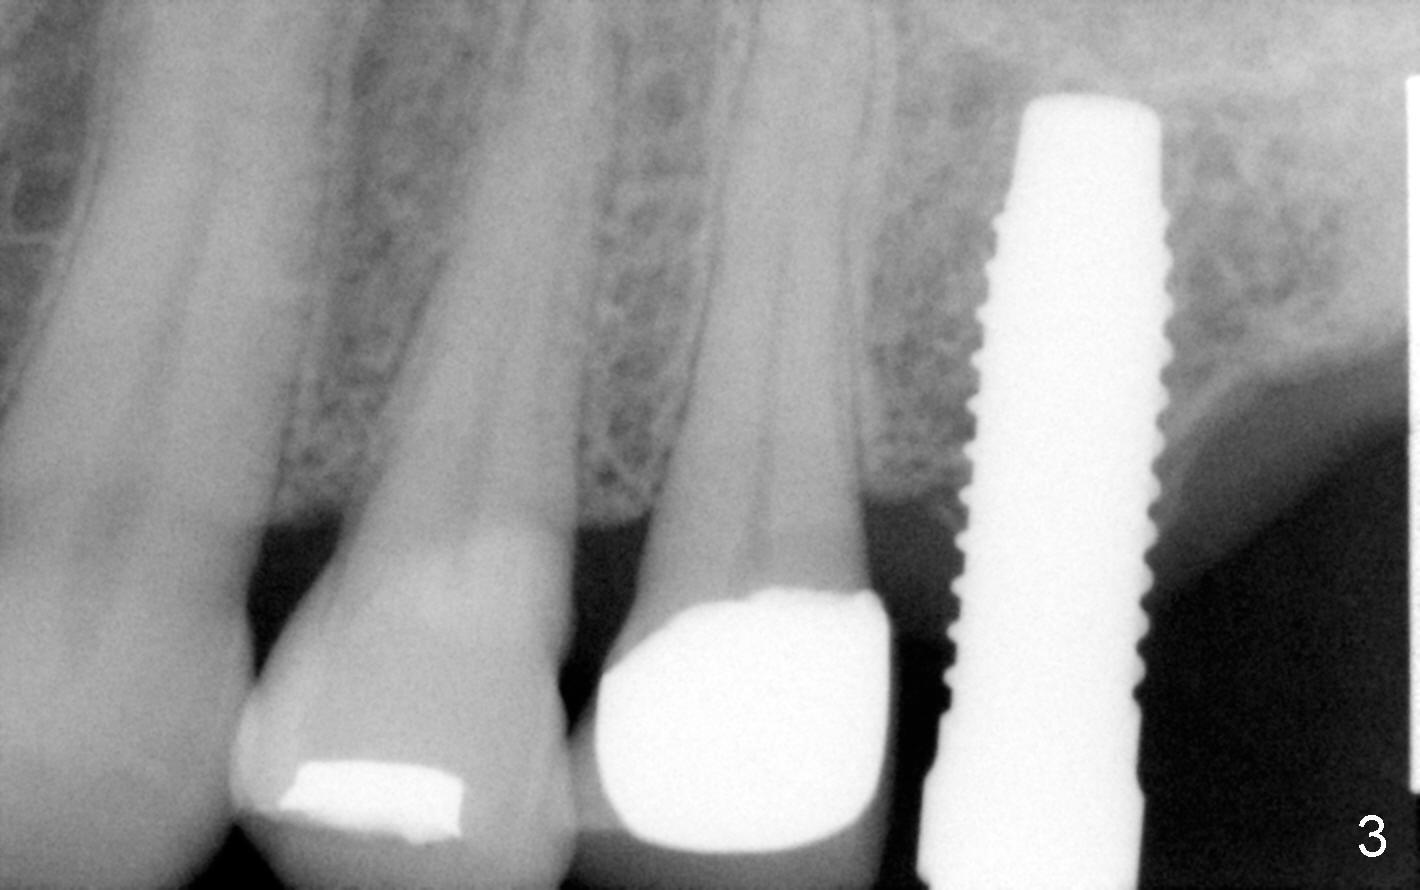

Fig.2 shows a 1.6 mm pilot drill at the depth of 11 mm; the tip of the drill penetrates the sinus floor. Bone expanders (2.6, 3.0, 3.4, 3.8 (Fig.3) and 4.3 mm) are used and alternated with tapered osteotomes (3 and 4 mm). The latter are used to break through the sinus floor. Then 4.5x14 mm and 5x14 mm taps are applied to create threads for implant. The second tap has some binding to the bone. Finally 5x14 mm tapered implant is inserted with more than 60 Ncm torque (Fig.4). Although the apical portion of implant (approximately 3 mm) pokes into the sinus, the patient does not experience nasal hemorrhage intra- or post-op.